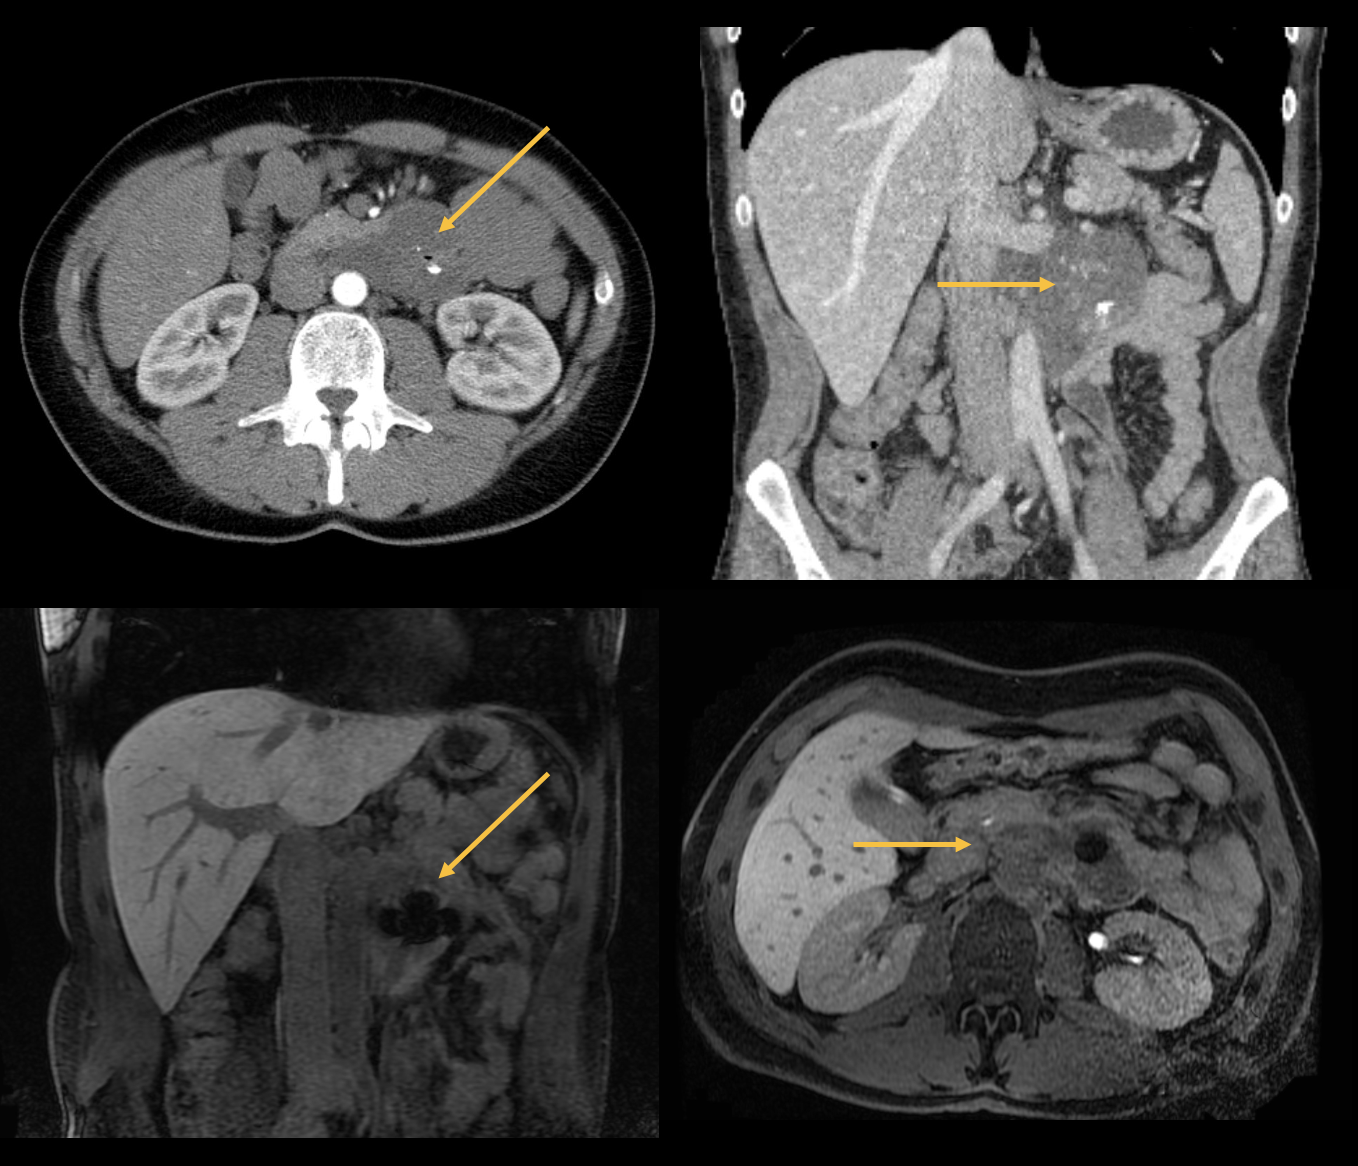

I pazienti con nausea e vomito persistenti dovrebbero sempre essere esaminati radiologicamente se i sintomi persistono per più di due settimane e la causa non è chiara, perché potrebbe essere presente una malattia rara. Il signor H. lamentava disturbi aspecifici come gonfiore, dolore addominale, nausea e anemia. La diagnostica per immagini (vedi foto) ha rivelato un tumore stromale gastrointestinale (GIST). Il GIST è un tumore semi-maligno del tratto gastrointestinale (in particolare dello stomaco e dell'intestino tenue), che può dare metastasi ma è solitamente associato a una buona prognosi. Il tumore si manifesta di solito nella mezza età (40-60 anni) e viene trattato chirurgicamente. In caso di metastasi, viene somministrata un'immunoterapia adiuvante con un inibitore della protein-chinasi.

image5.png

Figura 3: Immagini TC e RM assiali e coronali. GIST che origina dalla pars horizontalis duodeni, ventralmente alla vena renale sinistra e adiacente alla coda pancreatica. Artefatti di suscettibilità centrali con inclusioni aeree e calcificazioni.